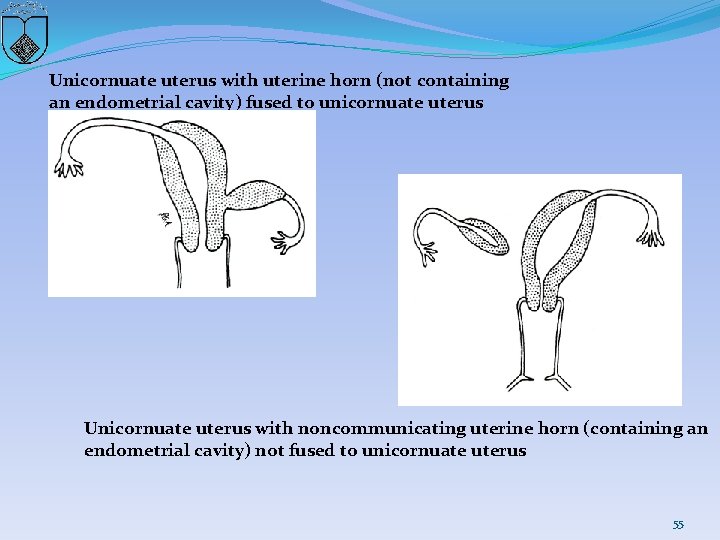

Unicornuate uterus with uterine horn (not containing an endometrial cavity) fused to unicornuate uterus Unicornuate uterus with noncommunicating uterine horn (containing an endometrial cavity) not fused to unicornuate uterus 55